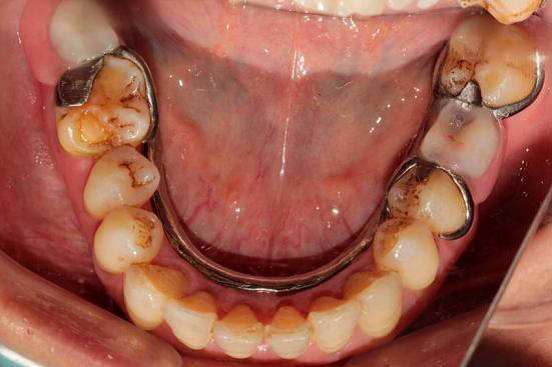

检查: 口腔卫生条件可,CI=1, DI=1,牙龈无充血肿胀,BOP(-),牙龈退缩约0.5~1mm,未探及深牙周袋,PD:3~4mm;口腔黏膜色性质正常, 舌体大小、形态、活动度正常。 36、47缺失,右侧下颌为游离端缺失,缺牙区近远中间隙及HE龈间隙可;剩余牙槽嵴吸收呈I型,高圆形;35、37牙体未见明显缺损,叩(-),松(-),46近中颊HE面有一大面积磨耗,探(-),叩(-), 松(-),上下前牙切端不同程度磨耗,并有不同程度的黄染,16远中HE面有一大面积黑色色素沉着,探(-),叩(-),松(-)

诊断:1. 下颌牙列缺损(Keneedy II类 I亚类) 2. 慢性牙周炎 处理: 取上下颌研究模型,行RPD设计, 根据设计进行牙体预备,取模,试戴钛支架,比色,试戴RPD,复查。

美观性差是可摘局部义齿修复的一个缺陷。传统的卡环要通过尽可能的环抱基牙来或的固位,在张口动作时很容易暴露唇颊侧的金属卡环,然而美学卡环的出现恰恰能一定程度上解决了这个问题。